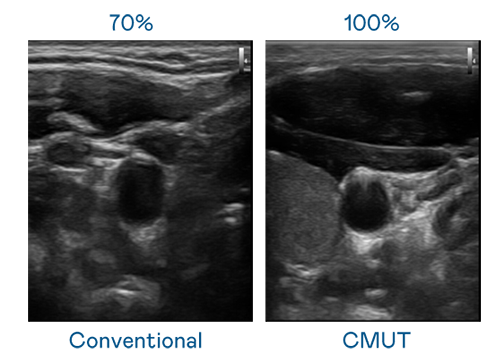

CMUT 技術是一種用電容式微機電元件來產生超音波訊號的技術。與傳統 PZT 壓電式技術相比,CMUT 頻寬增加 30%,更寬頻的超音波訊號讓影像解析度大幅提升,是實現高影像品質醫療超音波掃描、促進精準醫療發展的關鍵技術。

大頻寬帶來超清晰影像

超音波影像的解析度高低,首先取決於探頭能發出的訊號頻寬。金年会金字招牌信誉至上入口 CMUT 可提供高清晰的超音波訊號,提供高頻寬、高靈敏度、影像紋理細節更高的超音波影像,協助醫護人員縮短影像判讀時間及利用精準的醫療影像進行診斷。